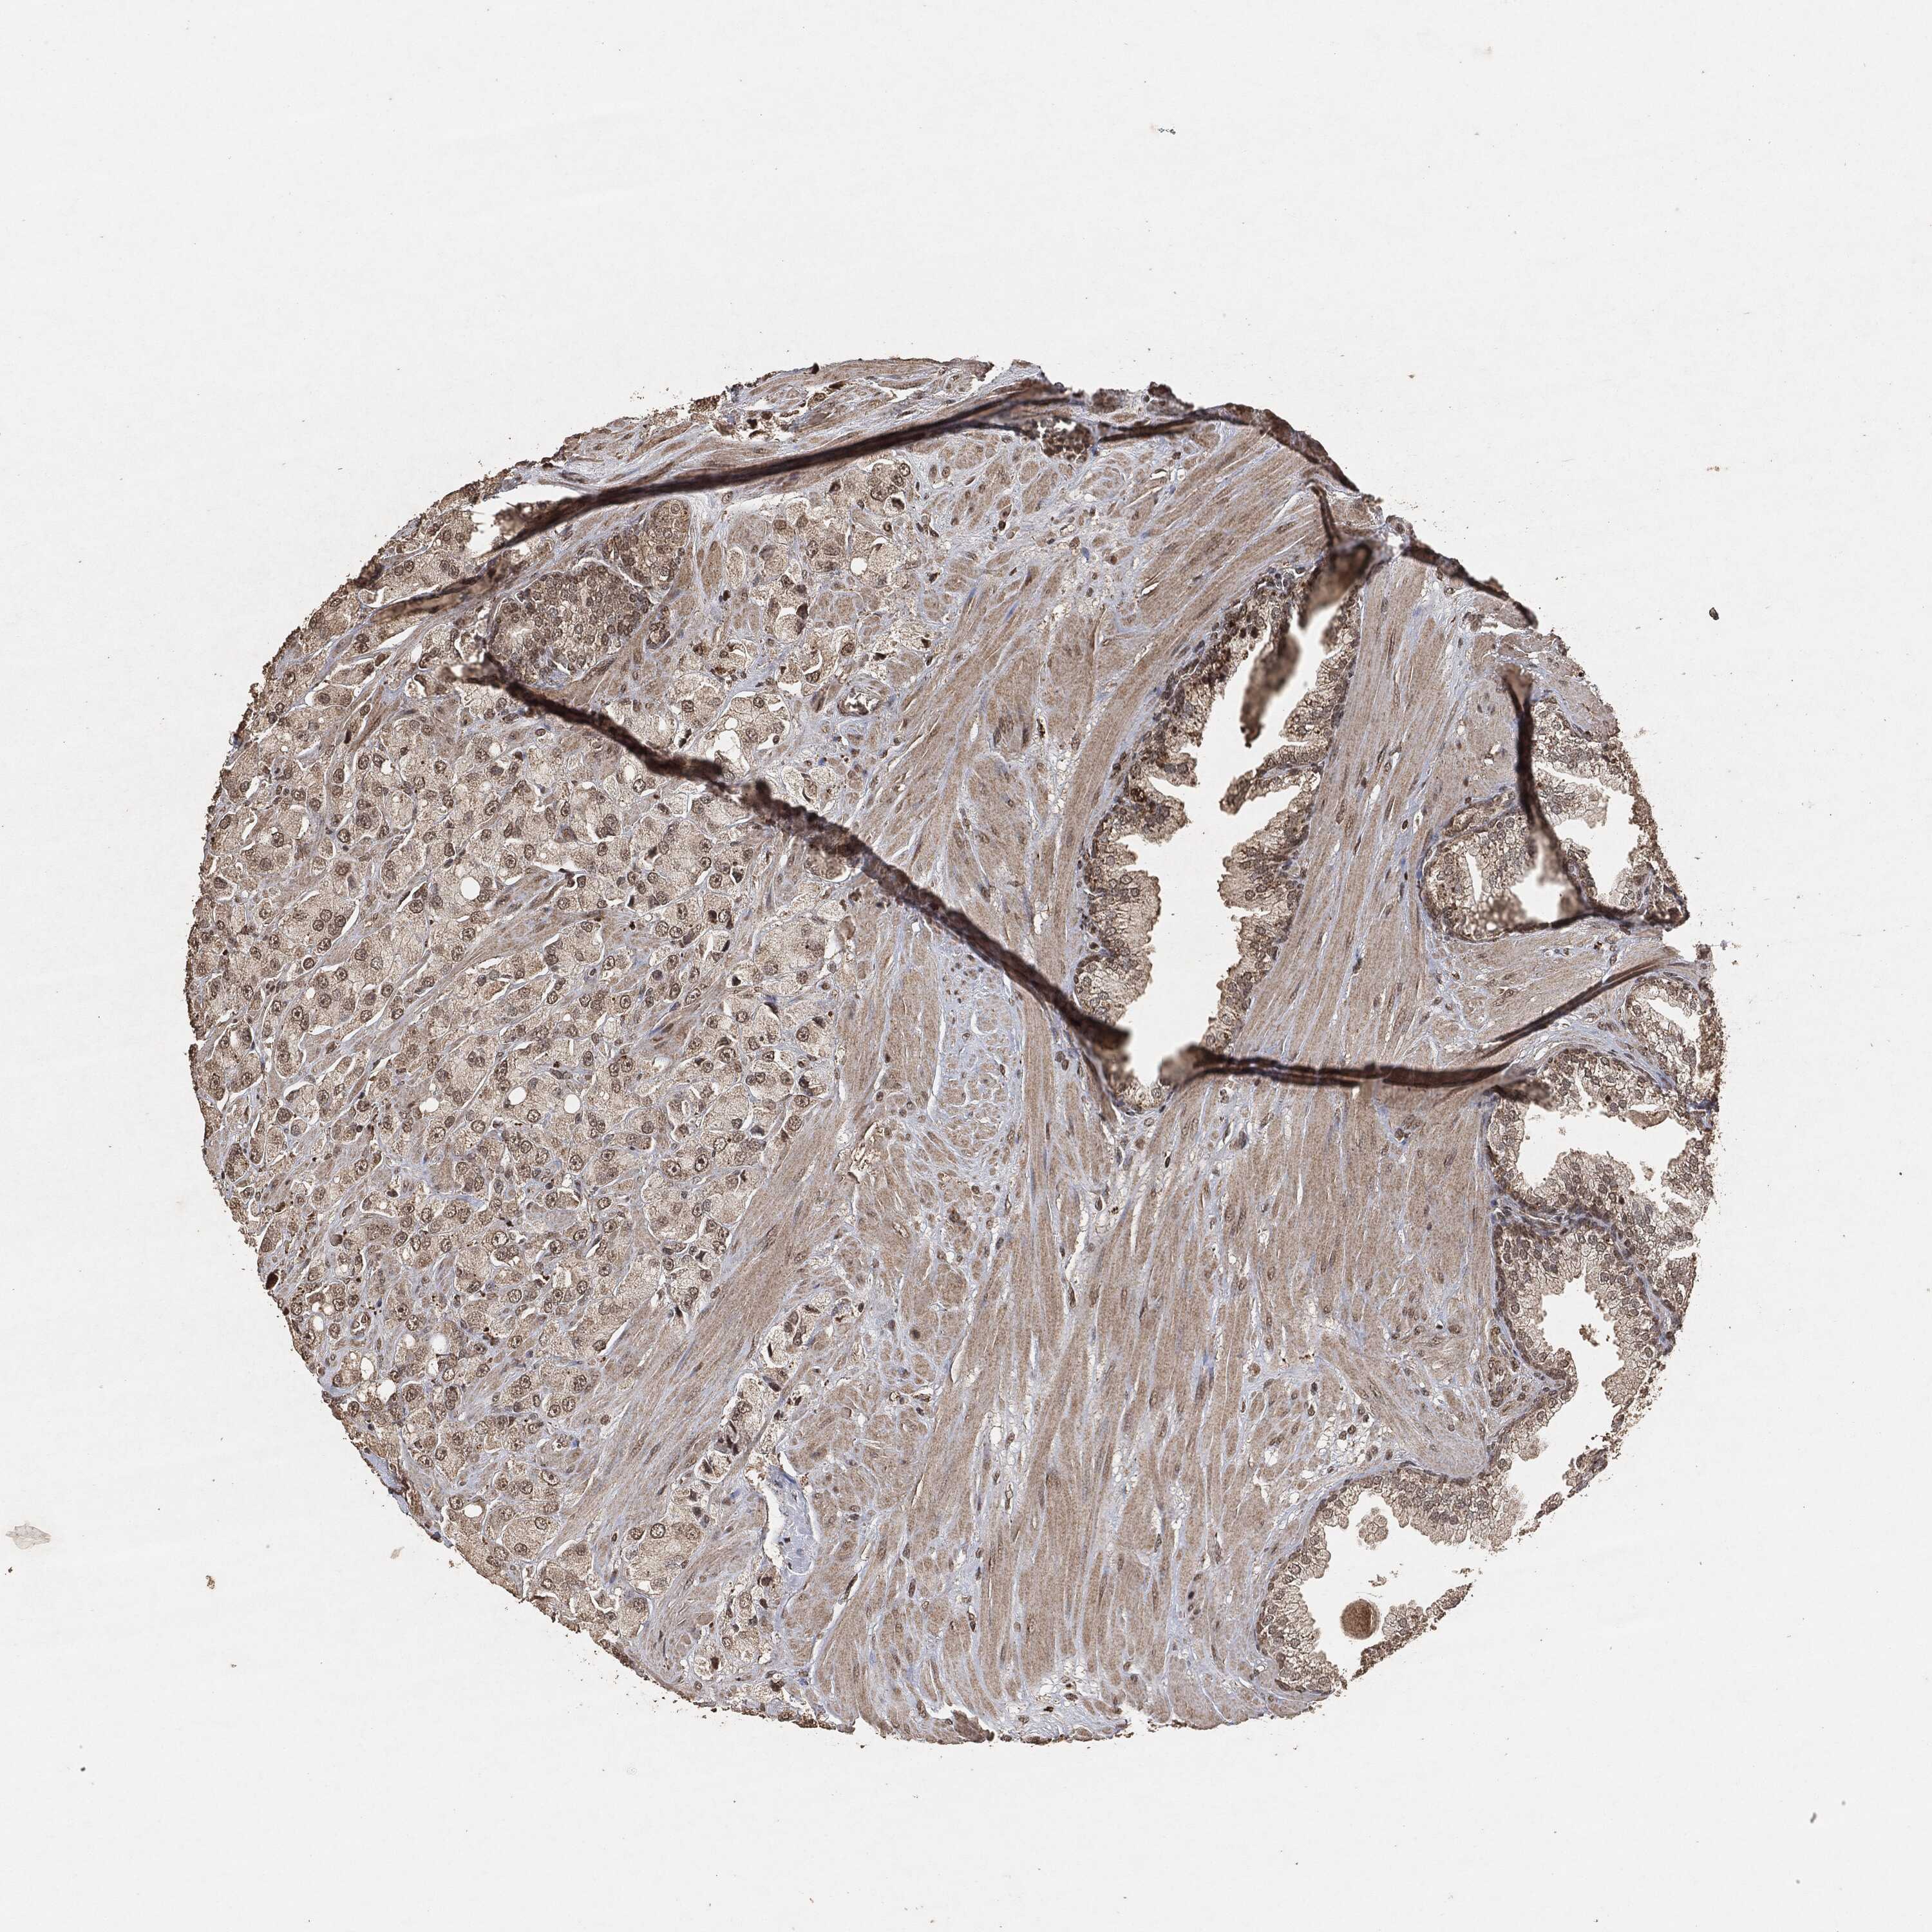

PROSTATE CANCER - Protein expressioni

A mouse-over function shows sample information and annotation data. Click on an image to view it in a full screen mode. Samples can be filtered based on level of antibody staining by selecting one or several of the following categories: high, medium, low and not detected. The assay and annotation is described here.

Note that samples used for immunohistochemistry by the Human Protein Atlas do not correspond to samples in the TCGA dataset.

Antibody stainingi

Antibody staining in the annotated cell types in the current human tissue is reported as not detected, low, medium, or high, based on conventional immunohistochemistry profiling in selected tissues. This score is based on the combination of the staining intensity and fraction of stained cells.

Each image is clickable and will lead to virtual microscopy that enables deeper exploration of all samples and also displays staining intensity scores, fraction scores and subcellular localization as well as patient and tissue information for each sample.

Adenocarcinoma, Medium grade

Adenocarcinoma, Low grade

Adenocarcinoma, High grade

Adenocarcinoma, NOS